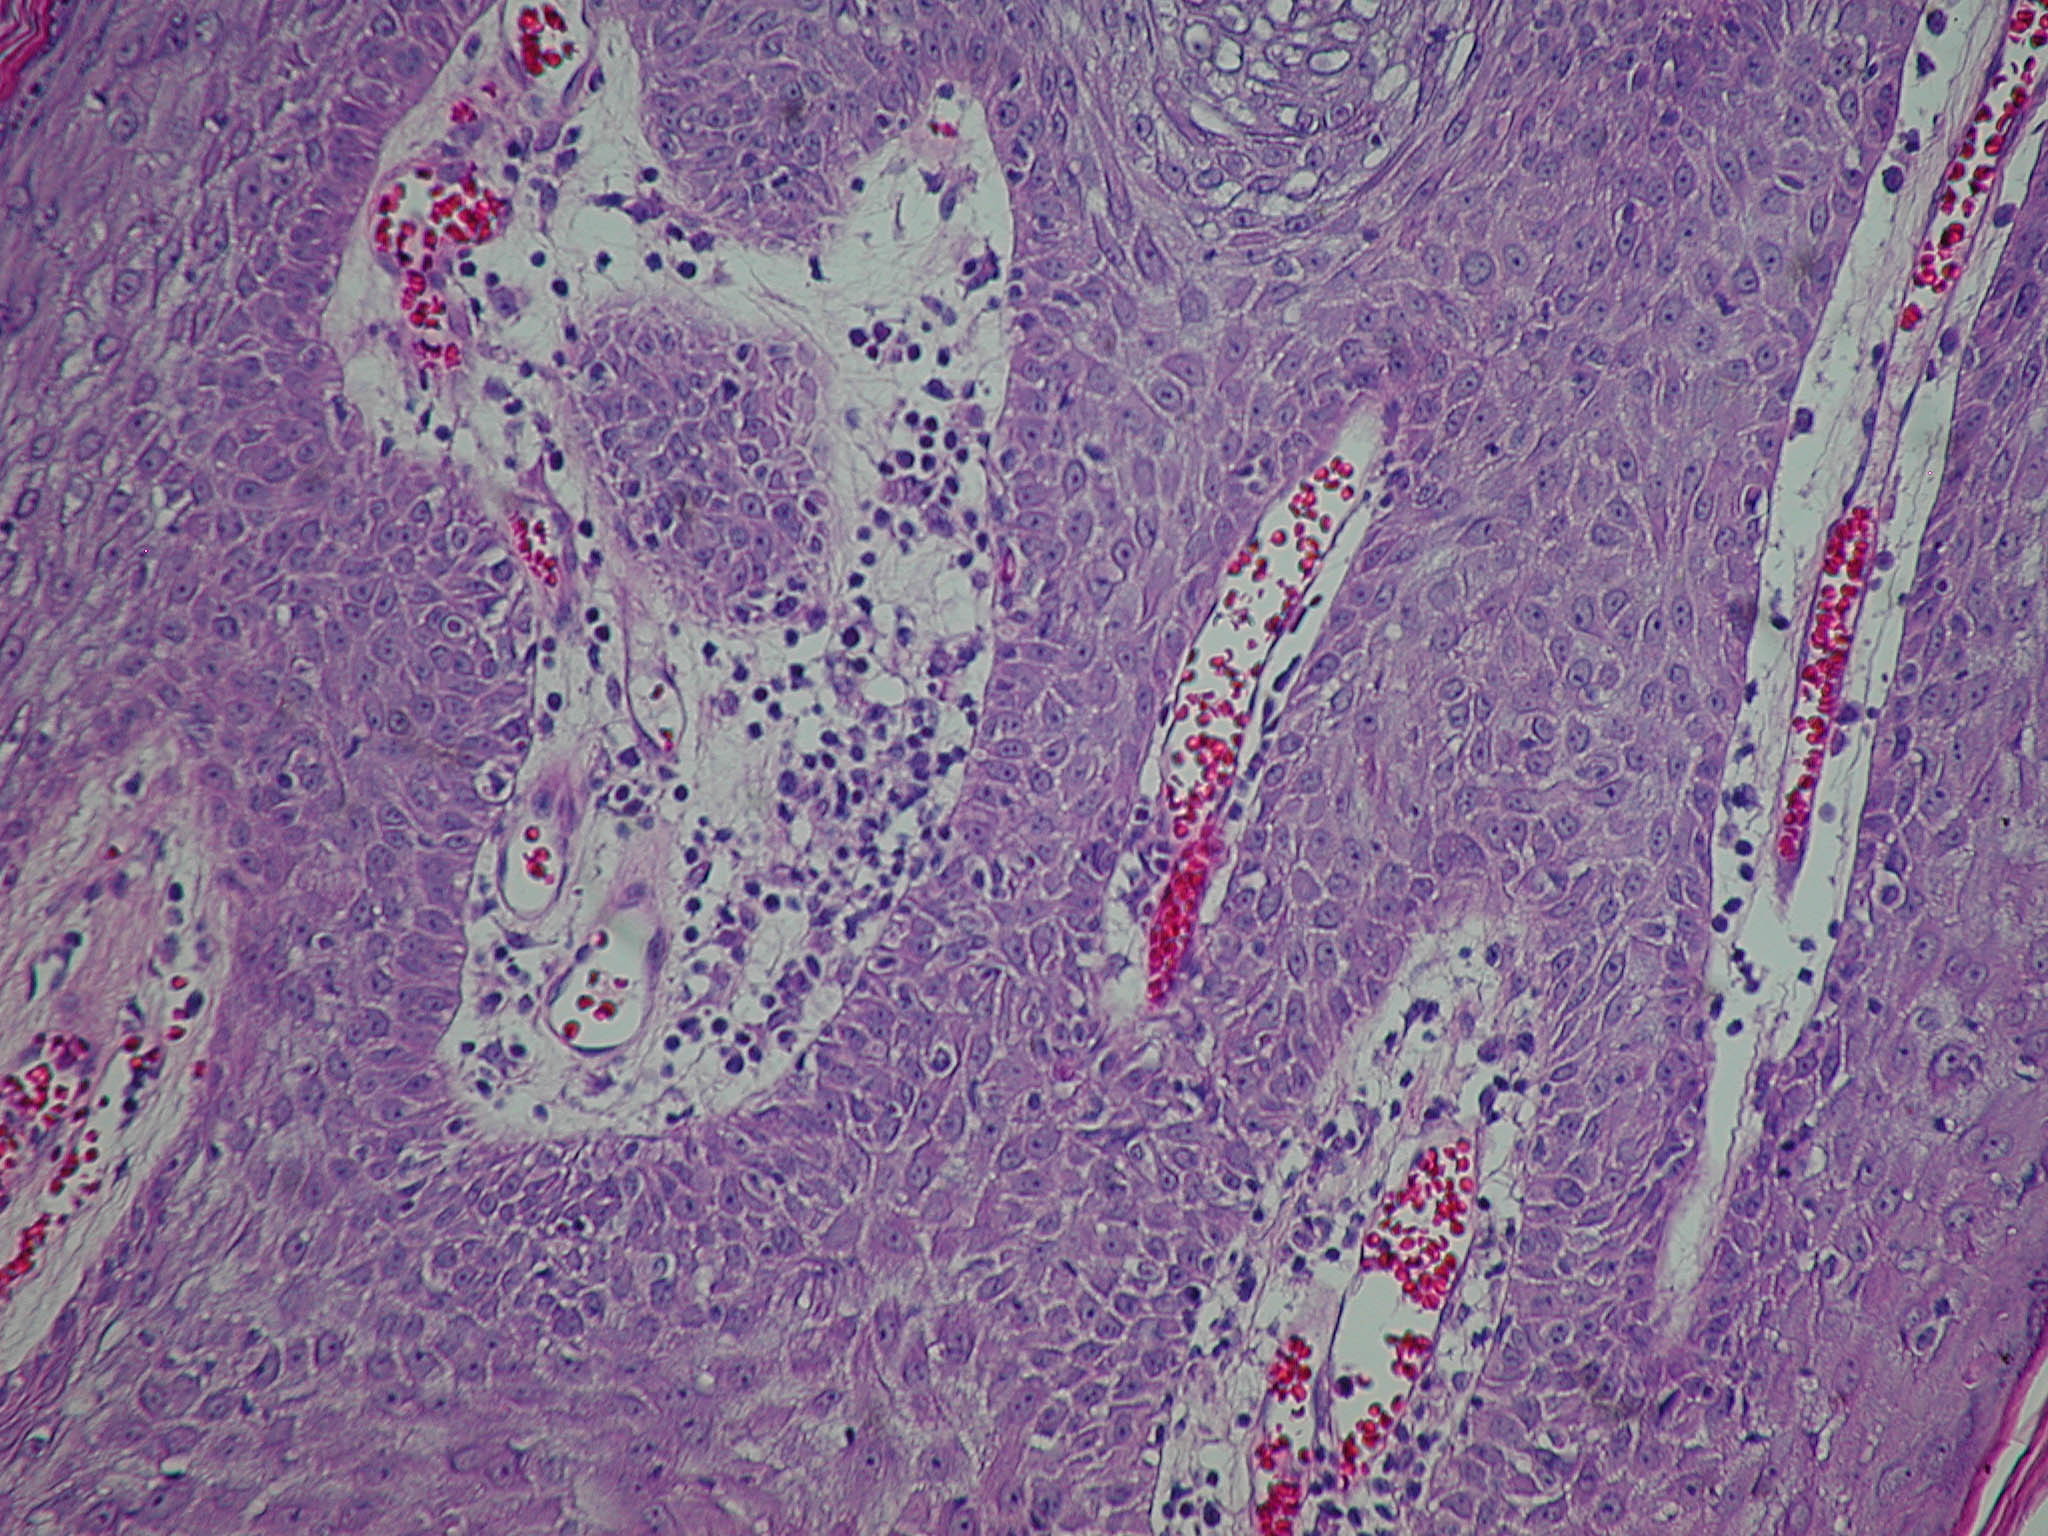

Atlas of skin histopathology

Seborrheic keratoses = التقران الدهني